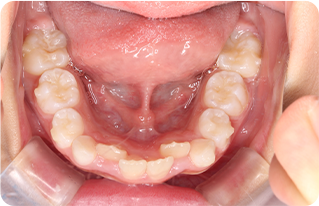

歯並びが悪いと、歯ブラシが届かず、歯垢や食べカスがたまりやすくなるため、虫歯や歯周病のリスクが高まります。小児期に歯並びを整えることで、歯並びの悪さによる虫歯や歯周病のリスクを軽減することができます。

歯並びが良くなることで、口腔内の清潔についても改善され、虫歯や歯周病などの口腔内疾患のリスクを軽減することができます。また、歯並びが良くなることで、咀嚼機能が向上し、消化器官の負担を減らすこともできます。